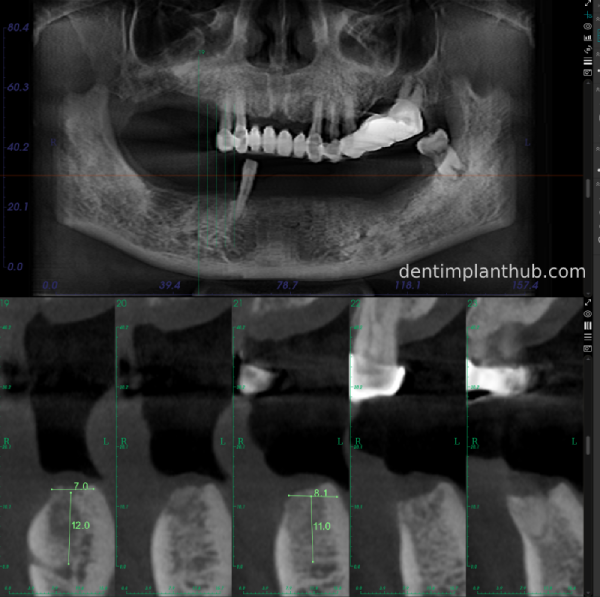

A review of the CBCT on 6/10/23 was more promising and a surgical plan was subsequently drawn up.

46

44

42

32

34

36

General schematic of the surgical programme

Detailed list of implant types and composite abutments to be prepared.

46 tooth position, implant model number 4810, RC series straight composite abutment;

44 tooth position, implant model number 4110, RC series straight composite abutment;

42 tooth position, implant model number 4110, RC series straight composite abutment; alternate implant model number 3310, alternate NC series straight composite abutment;

32 tooth position, implant model number 4110, RC series straight composite abutment; alternate implant model number 3310,. Alternate NC Series Straight Composite Abutment;

34 Dental Position, Implant Model No. 4110, RC Series Straight Composite Abutment;

36 Dental Position, Implant Model No. 4808, RC Series Straight Composite Abutment;